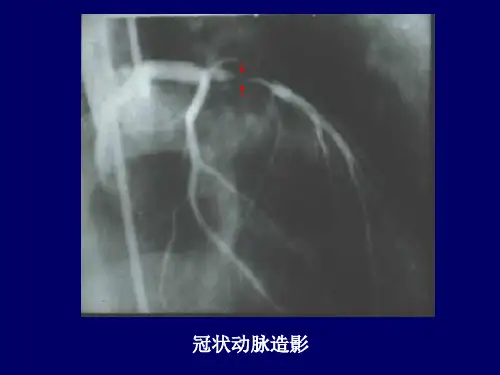

冠状动脉造影:

严重稳定型心绞痛(CCS3级),药物不能控制症状 CCS1~2级,有心梗病史或低负荷状态下即有心肌 缺血表现心绞痛伴束支传导阻滞,核素检查证实易诱

发缺血者 严重室性心律失常者